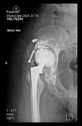

The radiological examination allowed us to verify the close bone-to-implant contact and the unchanged position of the implant during follow-up.

In all the cases operated with the above-described targeting procedure, the stems of the cups remained between the cortical bone surfaces without perforation of the linea terminalis, as shown by postoperative radiographs. There were no complicated surgical situations. In 16 cases, the wound healings were uneventful, and the hips were able to bear weight again after postoperative rehabilitation.